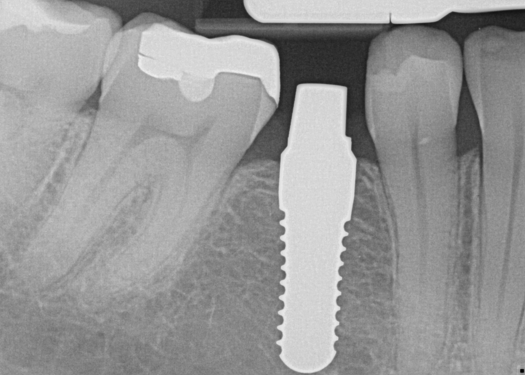

Fig 8. Preoperative periapical radiograph.

Figure 8

Fig 9. 12-week postoperative periapical radiograph.

Figure 9

Essentially, after integration and evaluation of soft tissue at 12 to 16 weeks subsequent to surgical placement of the ceramic implant, the implant is treated similarly to a natural tooth receiving a long-term restoration, and the protocol is the doctor's choice for soft-tissue management at the time of the final impression. Radiographic examination in Figure 8 and Figure 9 revealed that bone volume and soft tissue were preserved, primarily due to exceptional biocompatibility and the PRF biologics implemented after the atraumatic extractions.